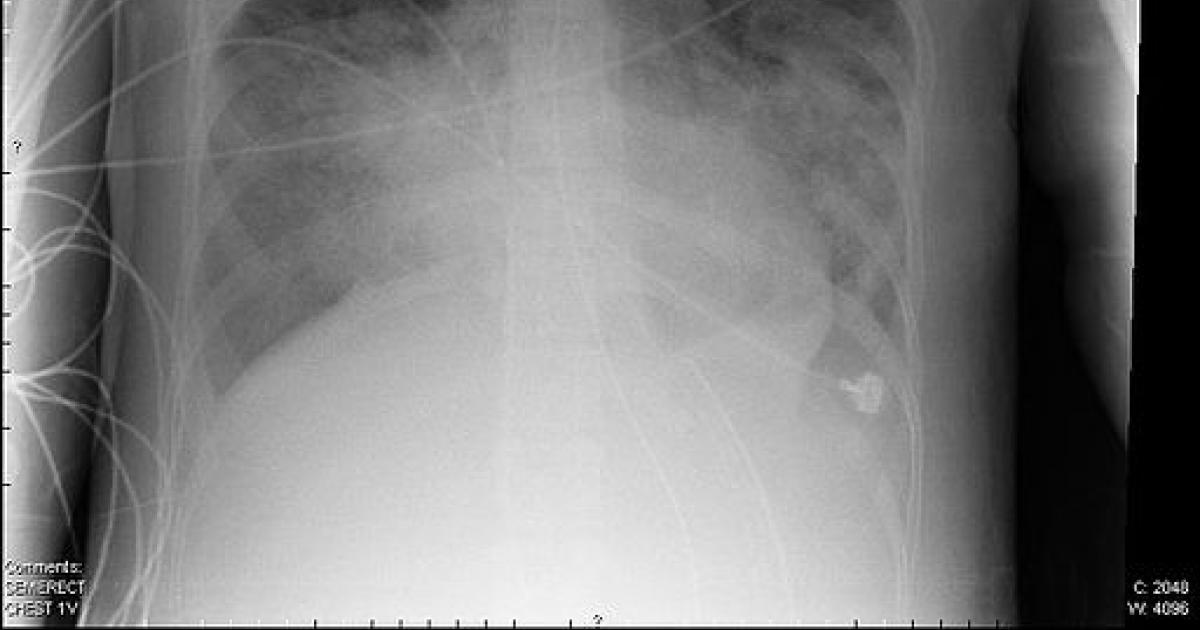

Acute respiratory distress syndrome, ARDS, is a final pathway for many infectious and traumatic events. The response of the lungs, in this case, to coronavirus, is to summon the immunologic cavalry. The immunologic response unintentionally thickens those alveolar membranes, making it more difficult for oxygen to diffuse. The inability to deliver oxygen from the bloodstream to our organs will subsequently cause them to fail over time, tightening the death spiral. [1]

The thickening of the alveoli makes the lung stiffer, creating more work for our respiratory muscles to expand the lung during inhalation; and reducing the elastic recoil of the lungs that expels air with exhalation. These two effects cause the tidal volume to fall. The rate of breathing increases to compensate, but the muscles already under additional stress, tire; you cannot breathe rapidly, termed tachypnea, for long periods. Mechanical ventilation seeks to restore adequate oxygenation